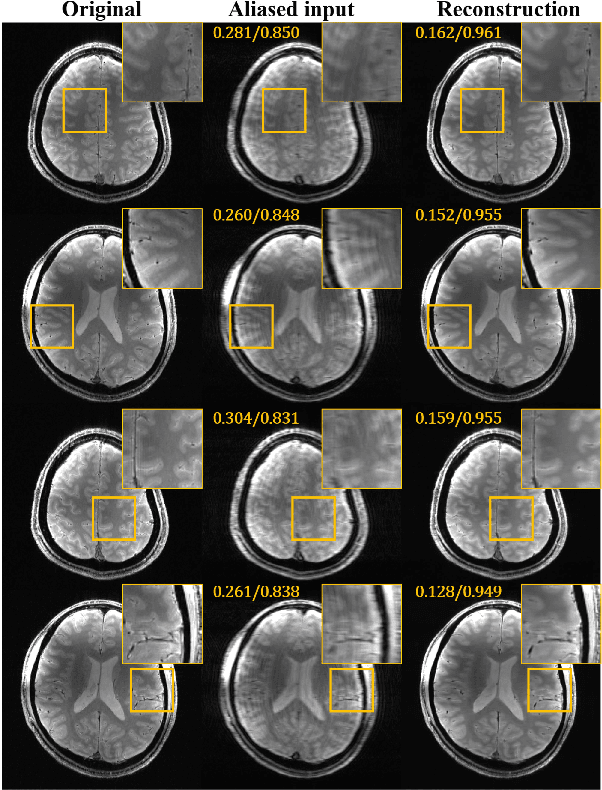

Abstract:Accelerated magnetic resonance (MR) scan acquisition with compressed sensing (CS) and parallel imaging is a powerful method to reduce MR imaging scan time. However, many reconstruction algorithms have high computational costs. To address this, we investigate deep residual learning networks to remove aliasing artifacts from artifact corrupted images. The proposed deep residual learning networks are composed of magnitude and phase networks that are separately trained. If both phase and magnitude information are available, the proposed algorithm can work as an iterative k-space interpolation algorithm using framelet representation. When only magnitude data is available, the proposed approach works as an image domain post-processing algorithm. Even with strong coherent aliasing artifacts, the proposed network successfully learned and removed the aliasing artifacts, whereas current parallel and CS reconstruction methods were unable to remove these artifacts. Comparisons using single and multiple coil show that the proposed residual network provides good reconstruction results with orders of magnitude faster computational time than existing compressed sensing methods. The proposed deep learning framework may have a great potential for accelerated MR reconstruction by generating accurate results immediately.